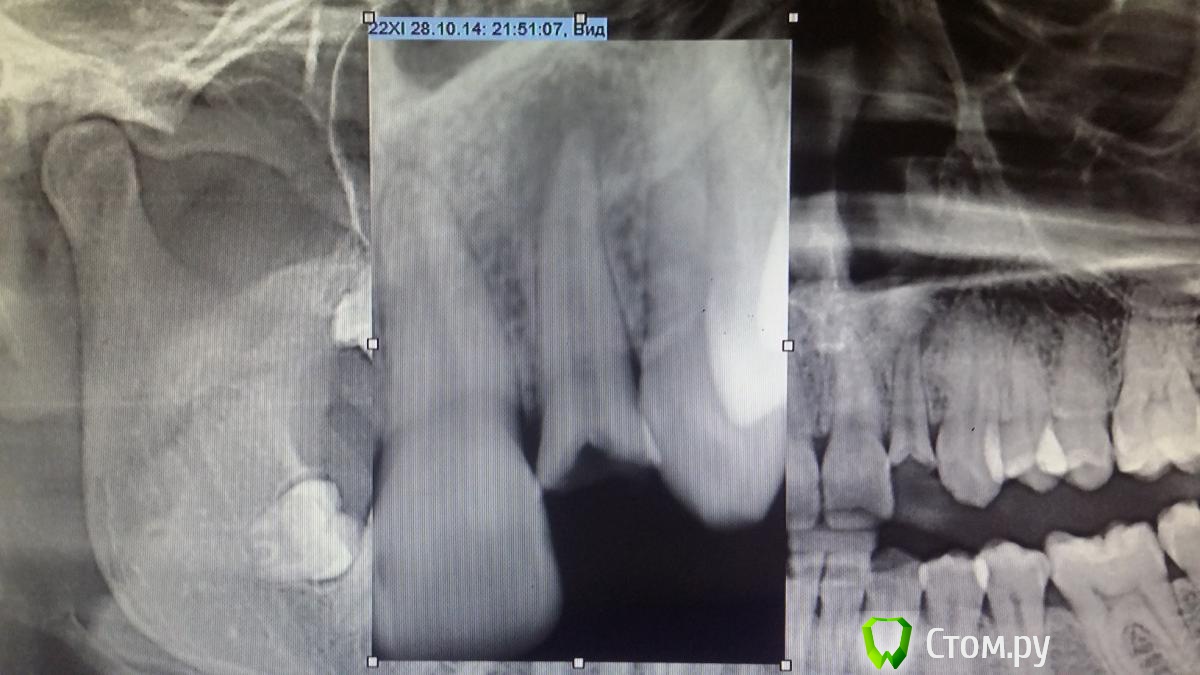

Recive Опубликовано 1 ноября, 2014 Поделиться Опубликовано 1 ноября, 2014 Обратилась с жалобами на скол зубаранее(со слов пациентки 1 год назад) лечила в государственной клинике.в кк паста, эндометазон или резорцин формальная, корень зуба изменен в цвете.Товарищи вопрос:рационально ли протезирование после резекции верхушки зуба?сколько там останется корня ? Назначил на кт.Хирург боится имплантировать отсроченно., боится сростания гребня и отсутствия кости. Ссылка на комментарий

Сева северный Опубликовано 23 ноября, 2014 Поделиться Опубликовано 23 ноября, 2014 Я за простые решения ...судя по снимку пломбированием и не пахло? Да и здоровый дентин и ферул видимо присутствует.Учитывая возраст консервативная тактика предпочтительна. Эндолечение через гидроокись. 2 недели ..ЕСЛИ ВСЕ СПОКОЙНО..Постоянное пломбирование. культевая вкладка, коронка .Контрольный снимок через пол года. Все! Лет на 15 должно хватить. Ссылка на комментарий